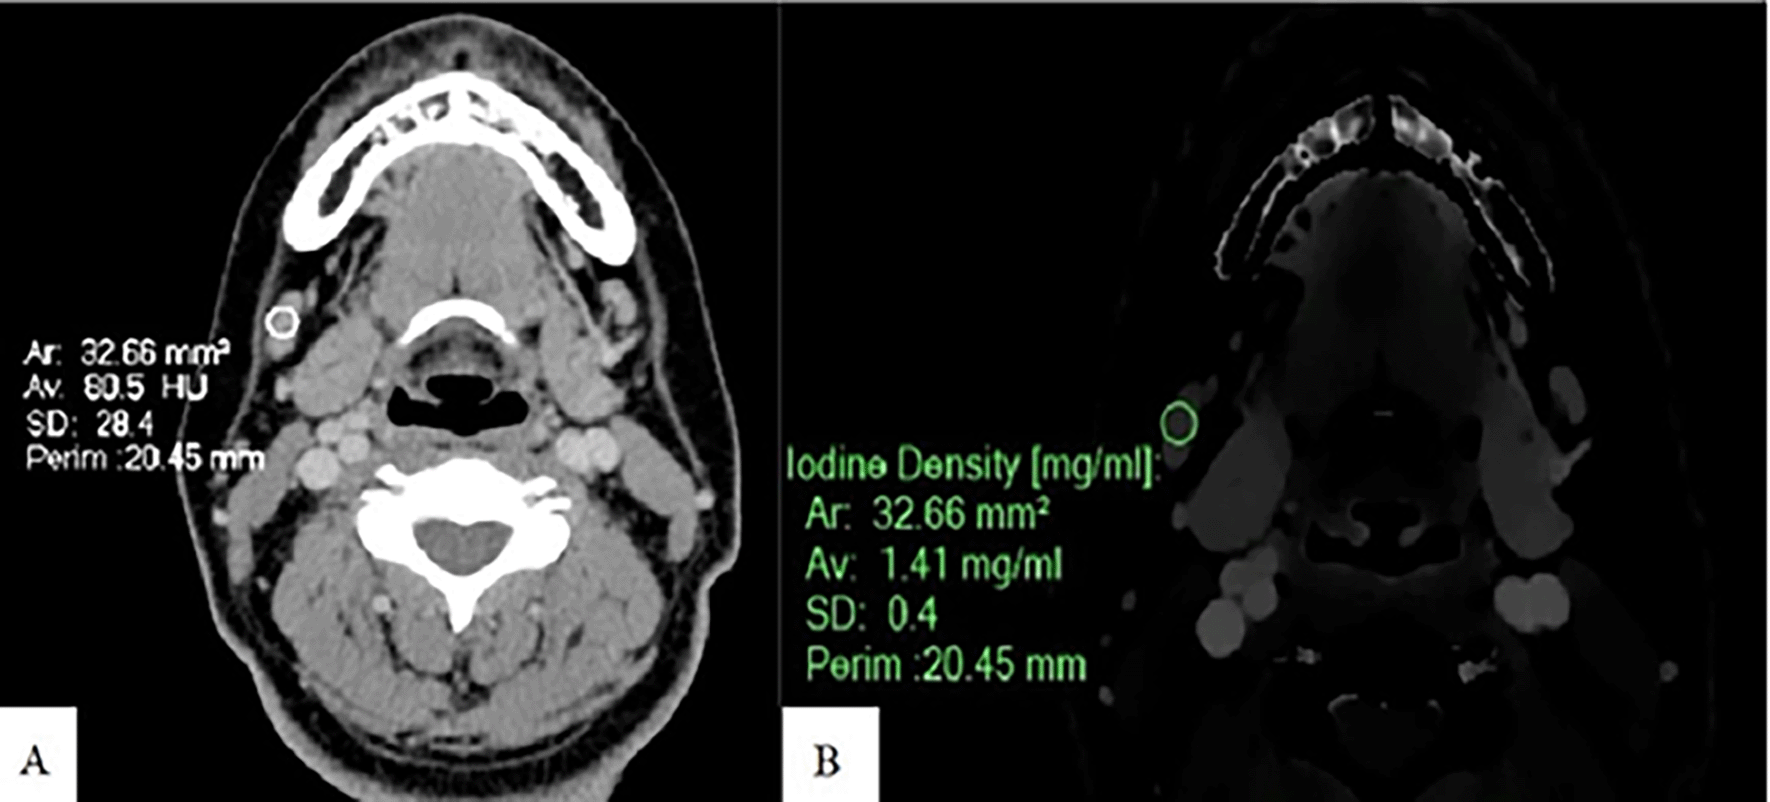

Spectral post-processing workstation (IntelliSpace Portal v11, Philips Healthcare, Netherlands) was used togenerateID and contrast-enhanced images (Figures 1, 2, and 3).

ID and CEAV were measured by placing rounded or oval-shaped regions of interest (ROI) on axial images in which lymph nodes appeared the largest (Figures 1, 2, and 3). All lymph nodes were evaluated by a radiologist with 15 years of experience in head and neck imaging. The most prominent nodes (3 nodes maximum) of each patient were selected. The average ID and CEAV values of each patient were recorded.